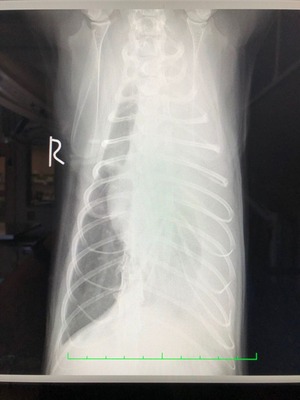

基本的に診断はレントゲンとエコー(胸水の採取)です。

これが膿胸症例のレントゲン写真です。

片方の肺が真っ白になって見えなくなってしまっています。

実際には肺はこの中に存在するのですが、大量に膿が貯留することで見えなくなってしまっているのですね。(レントゲンでは空気は黒く、液体はやや白く写ります)

これだけでは、胸水と鑑別ができませんので、次にエコーを用いて胸水の採取を行います。

そこで膿汁が採取されれば、『膿胸』と診断されるというわけです。

(肺炎や腫瘍の有無はまた別ですが…)